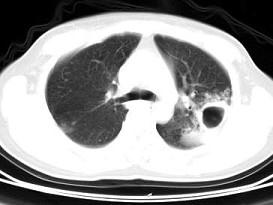

问题 男,25岁,咳嗽,咯血近一周,午后低热一月余,CT检查如图,最可能的诊断为 ( )

选项 A、肺大疱 B、肺炎 C、双上肺结核,左上肺结核空洞形成 D、液气胸 E、畸胎瘤

答案 C